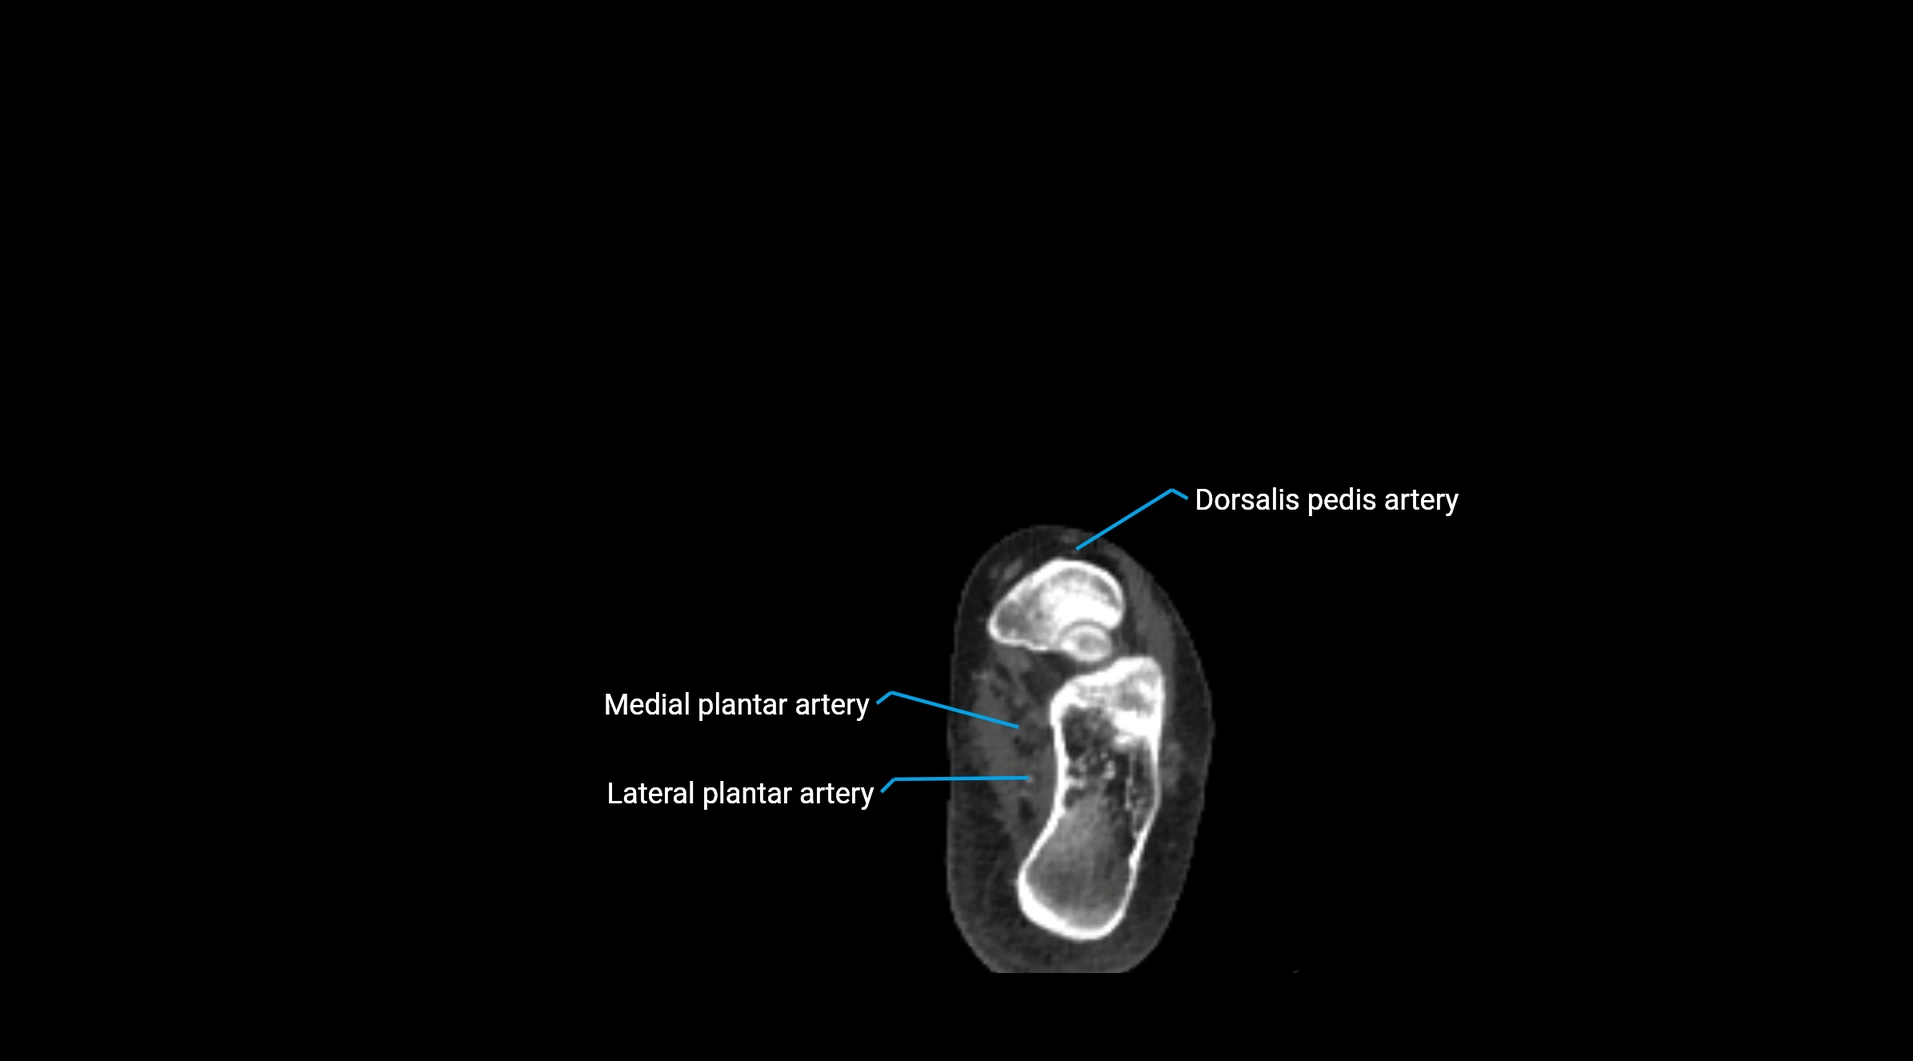

CT images

image

Contrast-enhanced CT (CTA):

• Gold standard for abdominal aortic imaging

• Provides excellent detail of lumen, wall, aneurysm, thrombus, and branch vessels